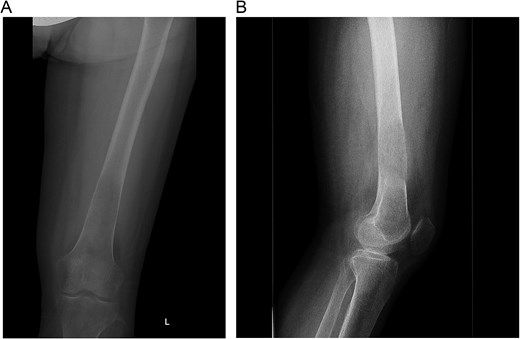

A multidisciplinary discussion involving orthopedic, maternal-fetal medicine, and head and neck teams determined the treatment plan. Further biopsy confirmed the brown tumor diagnosis, showing multinucleated giant cells, mononuclear stromal cells, bone resorption, and osteoclast clustering (Fig. 2A–C). Six days after the presentation, she was deemed suitable for parathyroidectomy. Although at high risk for pathologic fracture, she declined prophylactic fixation during pregnancy. Two days after a successful parathyroidectomy, she underwent an uncomplicated Cesarean section. As her calcium levels normalized, plans for femoral fixation were made post-childbirth. One week postpartum, the patient fell, resulting in a pathologic fracture of the left distal femur and ipsilateral iliac wing fracture (Fig. 3A and B).

(A and B) Pathologic fracture involving the left distal femur and left iliac bone.